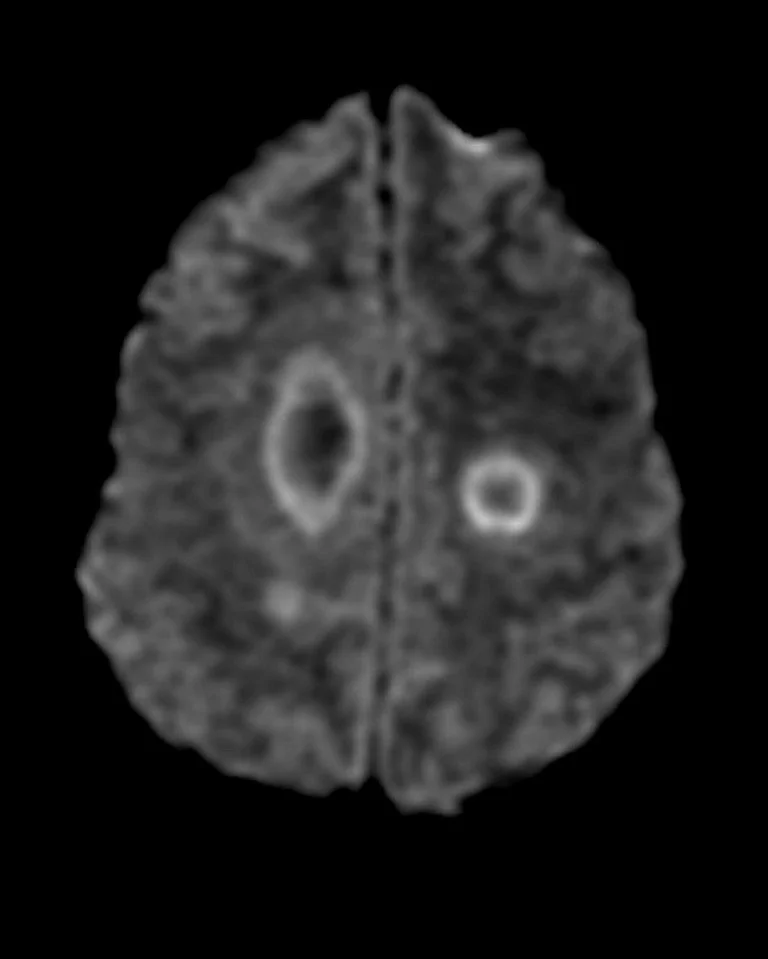

• DWI - peripheral restricted diffusion but not centrally

DWI showing peripheral restriction without central restriction

Peripehral open ring restriction on DWI not always seen as evidenced below